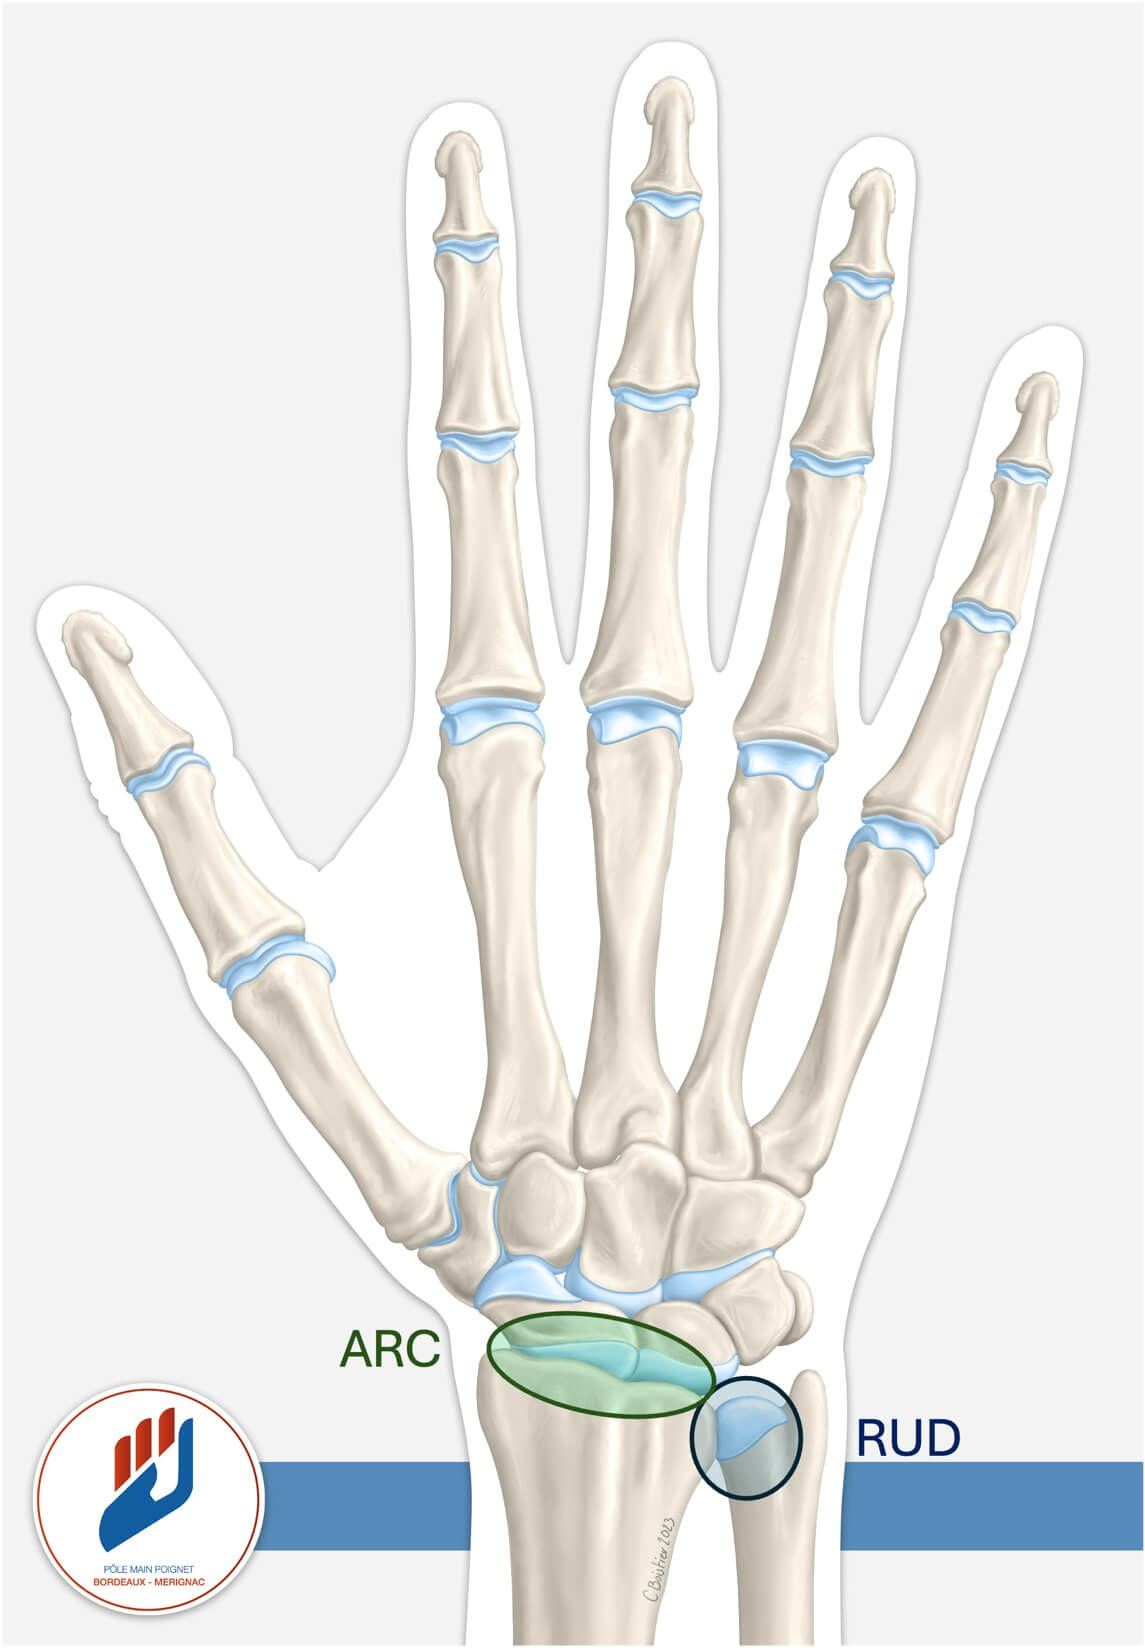

Le radius est l’un des deux os de l’avant-bras. Son extrémité distale participe à la formation de deux articulations essentielles pour le fonctionnement du poignet et de la main.

La première est l’articulation radio-carpienne (ARC), qui relie le radius aux os du carpe. Elle permet les mouvements principaux du poignet : la flexion, l’extension et les inclinaisons latérales. C’est elle qui permet d’approcher la paume vers l’avant-bras, de relever la main vers le haut ou de dévier le poignet vers le pouce ou le petit doigt.

La seconde est l’articulation radio-ulnaire distale (RUD), qui unit le radius et l’ulna dans leur partie terminale. Cette articulation est indispensable pour effectuer les mouvements de rotation de l’avant-bras : tourner la paume vers le haut (supination) ou vers le bas (pronation). Ces gestes paraissent anodins, mais ils sont indispensables pour des actions quotidiennes comme ouvrir une porte, tourner une bouteille, utiliser un tournevis ou simplement taper sur un clavier.